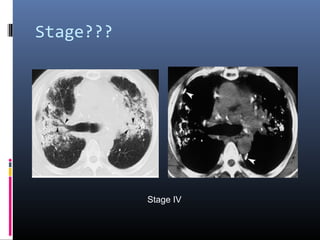

Stage???

stage IV

• #16 typical chest film of long standing sarcoidosis (stage IV) with fibrosis in the upper zones and volume loss of the upper lobes resulting in hilar elevation. Fibrosis results in obliteration of pulmonary vessels, which can lead to pulmonary hypertension.

• #17 Stage IV pulmonary sarcoidosis in a 48-year-old man. (a) Chest CT scan (lung window) demonstrates traction bronchiectasis (arrowheads) and fibrotic lesions with extensive calcification, findings that indicate stage IV disease. (b) Chest CT scan (mediastinal window) demonstrates calcification in the fibrotic lesions, mediastinal adenopathy, and irregularly thickened pleura (arrowheads).

• #18 Stage IV pulmonary sarcoidosis in a 60-year-old man. Chest CT scan demonstrates extensive fibrotic change and cavitary lesions with a central distribution (arrows) that distort the lung parenchyma. Irregular thickening of the pleura (arrowheads) and overinflation of the peripheral lung parenchyma are also seen.